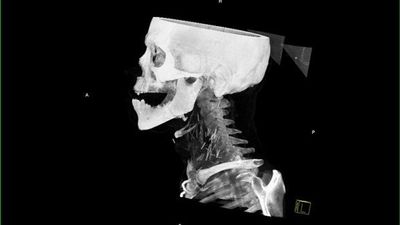

Pacienti i cili për një kohë të gjatë kishte qenë i varur nga heroina ka bërë një fotografim me rreze x, i cili ka zbuluar një të vërtetë të tmerrshme.

Fotografia e rëntgenit me rreze x ka nxjerr në pah dhjetëra gjilpëra të thyera në qafën e tij, ndërsa pas rekonstruimit të fotografisë në versionin 3D nga radiologët, është konstatuar se vërtetë bëhet fjalë për dhjetëra gjilpëra.

Mjekët besojnë se ky narkoman i cili sipas të gjitha gjasave nuk kishte pasur ku të shpohet në duar, dhe kështu kishte injektuar heroinën në venat e qafës.

Injektimi i heroinës në qafë mund ta lë pavetëdije narkomanin për disa sekonda, ku si pasojë gjilpëra mund të thyhet dhe një pjesë e saj të mbetet në qafën e tij.